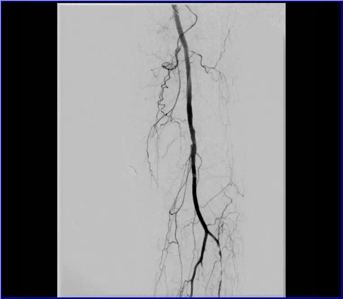

股動脈閉塞

糖尿病、高血壓、高脂血癥、吸煙、老年等原因都可以導(dǎo)致下肢動脈硬化、管腔狹窄、閉塞,引起一系列下肢缺血的癥狀。

早期癥狀:下肢感覺發(fā)涼,麻木,腿部肌肉出現(xiàn)痙攣,俗稱“抽筋”。

運動后疼痛:間歇性跛行,表現(xiàn)為行走一段距離后。

休息時疼痛:“靜息痛”,是下肢嚴重缺血的表現(xiàn),即使在不運動的情況下,養(yǎng)分供應(yīng)不能滿足組織的需要而出現(xiàn)疼痛,尤其在夜間疼痛加重,必須積極治療。

組織缺血壞死:嚴重時可導(dǎo)致肢體破潰、感染、壞死、發(fā)黑,最終需要截肢,甚至危及生命。